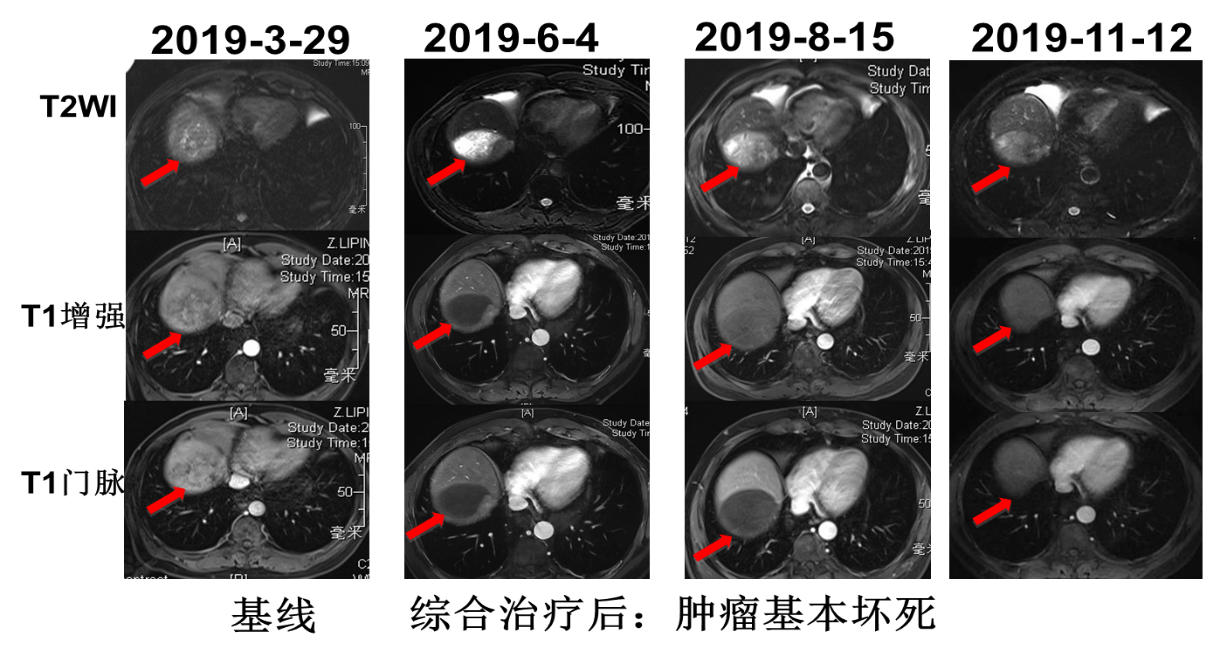

2019年4月2日行TACE+肝肿瘤微波消融术,5月6日起予以信迪利单抗治疗(200mg q3w ivgtt)联合仑伐替尼(12mg qd po),5月10日复查AFP降为正常(10.3ng/ml),PIVKA-Ⅱ降至3352 mAU/ml。6月4日复查肝脏MRI:mPR,局部强化结节,下腔静脉癌栓较前有所好转。7月2日再次行TACE术。术后于7月8日~9月16日行信迪利单抗注射4周期。8月15日复查MRI:mPR,强化结节好转,下腔静脉癌栓有所好转。8月19日复查PIVKA-Ⅱ进一步降至1202mAU/ml。11月12日复查AFP 12.4ng/ml,PIVKA-Ⅱ 1784mAU/ml,MRI提示病灶稳定。治疗经过见图2。MRI疗效评估见图3、图4、图5。

image004.png

图4. MRI疗效评估

患者为中老年男性,既往有乙型病毒性肝炎病史及抽烟史。2019年3月MRI检查发现右肝占位。肿瘤标志物检测结果AFP为418.8ng/mL;PIVKA-Ⅱ:40208mAU/ml,结合患者病史及影像学检查诊断为肝细胞癌。肿瘤的分期对于预后以及治疗方案的制定具有重要的指导作用,肝细胞癌的分期标准比较多,常用的有巴塞罗那(BCLC)分期和TNM分期,本例患者根据巴塞罗那分期定为C期;TNM分期为T4N0M0,IIIB期。患者的体能状态评价根据ECOG标准评分为0分;肝功能化验无明显异常,Child-Pugh 评级为A级。总体来说,患者肝脏病灶局限,无远处转移,并且体能状态以及肝功能良好,于2019年4月2日针对肝脏病灶行TACE+肝肿瘤微波消融术,术后1个月起(5月6日)信迪利单抗联合仑伐替尼治疗,5月10日复查肿瘤标志物明显降低。6月4日复查发现原病灶周边强化结节,于是再次行TACE治疗,术后继续给以信迪利单抗联合仑伐替尼治疗。2019年8月15日复查,MRI显示原病灶强化结节及下腔静脉癌栓有所好转。至11月12日,信迪利单抗治疗已10个周期,复查肿瘤标志物及MRI均提示病灶稳定。